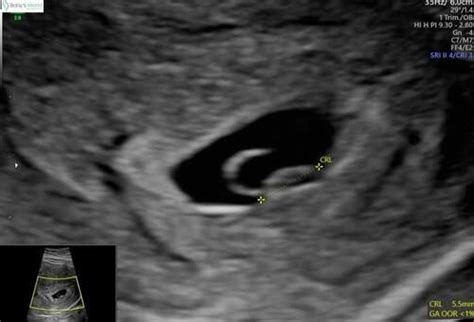

Het embryo is in deze fase van de zwangerschap nog klein, maar meestal al te zien op een echo. Hoe verder in week 6, hoe groter de kans dat u een kloppend hartje ziet. Ook ziet u waarschijnlijk een kleine dooierzak en een vruchtzakje bij 6 weken. De vruchtzak lijkt vroeg in de zwangerschap op een ring, daarom wordt het ook wel de zwangerschapsring genoemd.

Vanaf 5 weken zwangerschap kunt u de dooierzak op een vroege echo zien. Het zien van zo'n zakje is, naast een positieve zwangerschapstest, meestal een eerste bewijs van een beginnende zwangerschap. Een dooierzak ziet eruit als een rond of peervormig zakje. In de eerste weken van de zwangerschap is het zakje nog een stuk groter dan uw baby zelf. Tussen de 6 en 9 weken zwangerschap is het ongeveer 2 tot 3 millimeter groot. U ziet het op een echo naast het embryo zweven als een donker 'ringetje'. Het is ook mogelijk dat u op de echo twee of drie zakjes ziet; dan krijgt u een meerling!

Bij 5 weken zien we vaak: een vruchtzak met of zonder dooierzakje. Bij 6 weken zien we vaak: een embryo van 4-5 mm (wit vlekje) met een knipperend hartje. Bij 7 weken is het embryo te zien als een wit vlekje van ongeveer 9-10 mm.